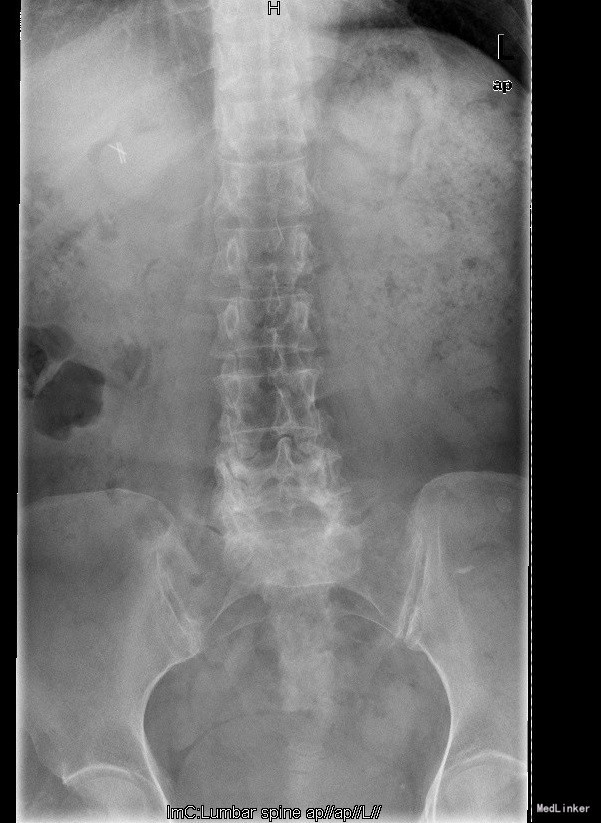

主诉:反复腰部疼痛20+年,加重伴双下肢胀痛麻木 现病史:患者于20+年前,因车祸行腰椎检查发现腰4椎体I°滑脱,并感腰部阵发性隐痛不适,一直未行特殊处理、4月前患者感腰部疼痛有所加重,并感双下肢阵发性胀痛麻木,久坐或弯腰后症状加重,以左下肢为甚,症状明显时难以直立行走,不伴畏寒发热、潮热盗汗等不适。10+天前患者在院外行理疗(具体不详),上述症状略有好转。在院外行腰椎x光摄片诊断为"腰4椎体II°滑脱,腰5椎体I°滑脱",故来我院就诊,门诊以"腰椎滑脱"收入住院

查体:脊柱外观无侧弯后突畸形,双下肢无肌肉萎缩。腰4-5、腰5骶1棘上棘旁轻压痛,伴左侧下肢放射;会阴部感觉未见异常,双侧小腿前外侧及足背足底感觉减退。腰椎前屈后伸及侧屈活动度正常;双下肢髂腰肌肌力4级,左侧直腿抬高试验阳性,加强试验阳性,左侧膝腱反射减弱,双侧病理征未引出。 辅助检查:院外腰椎正侧位片:腰4椎体II°滑脱,腰5椎体I°滑脱。

诊断:腰4椎II°滑脱症,腰5椎I°滑脱症 治疗:经后路腰4、5椎切开复位、椎管减压、Capstone椎间及后外侧人工骨+自体骨植骨融合、Legacy内固定术